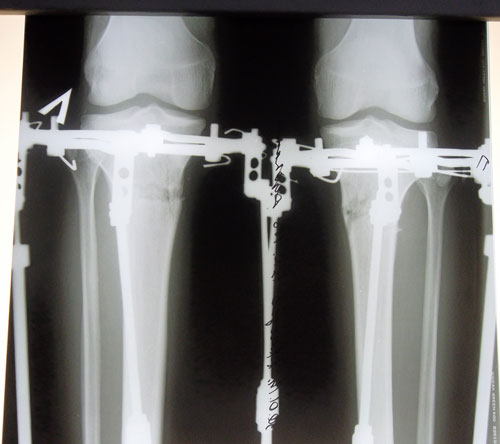

Дата операции 14.01.2014г.

Дата снятия аппаратов 15.04.2014г.

Срок лечения 3 месяца.